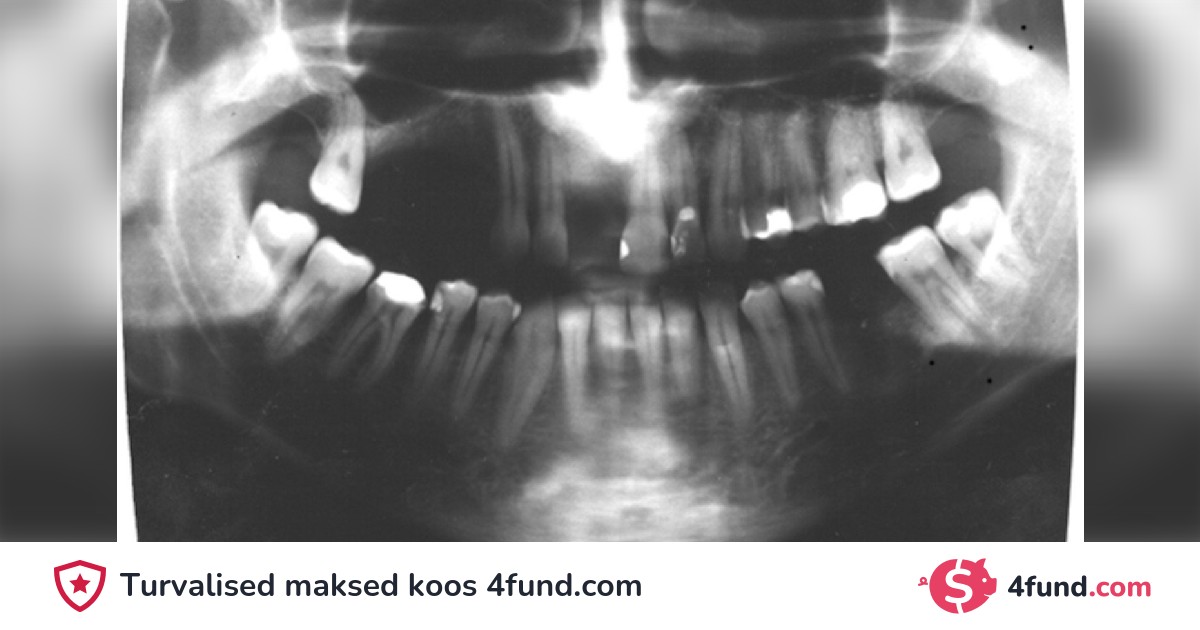

In 1992, a doctor extracted my tooth 2.4 and filed teeth 2.5 and 2.6 to replace the extracted tooth with a prosthesis, but part of the root of the tooth breaks and remains on the arch because the doctor did not check the extracted tooth.

10 years later, the rest of my remaining tooth destroyed an arch!